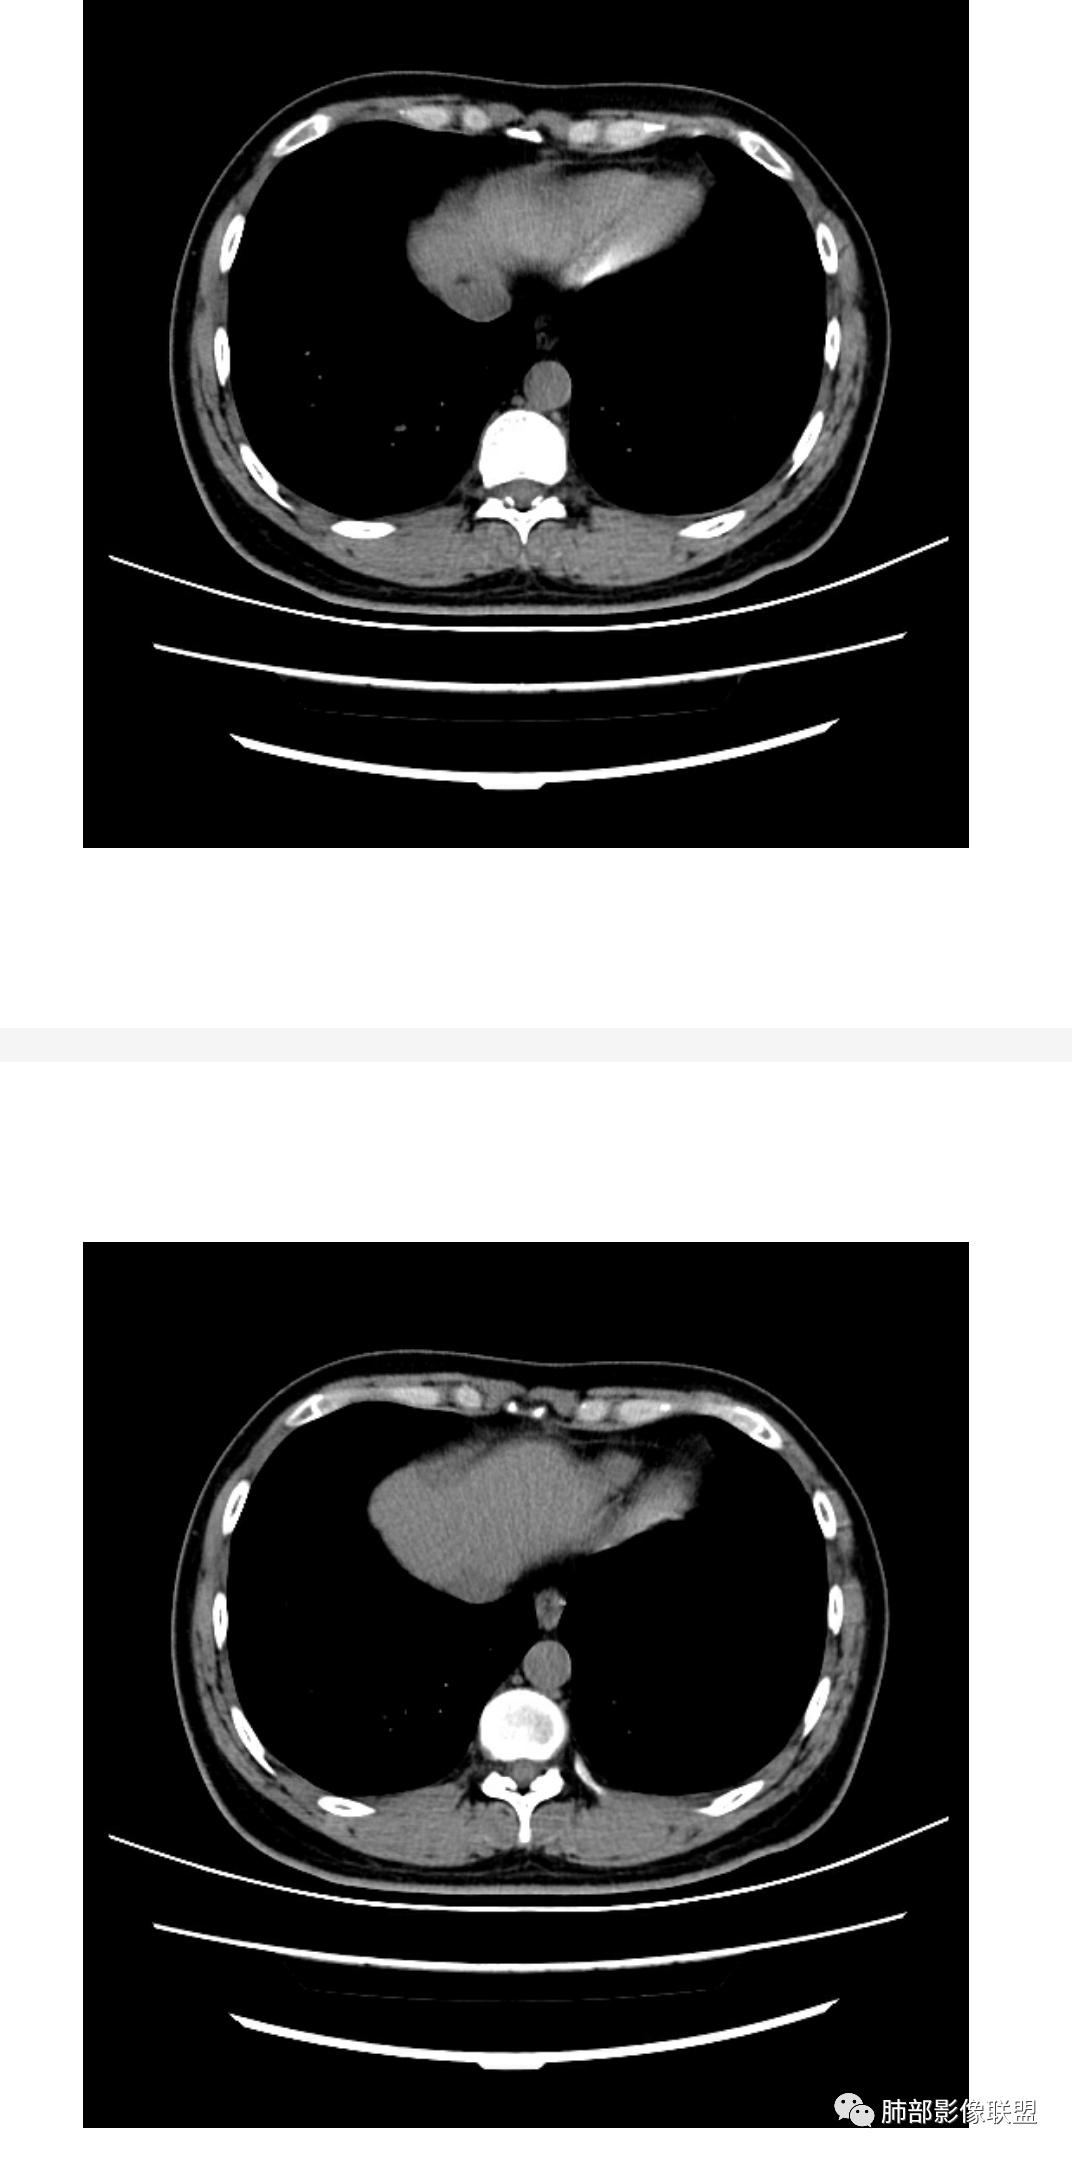

2、类型:常见有孤立肉芽肿型、肺炎实变型、混合型(多发结节/实变/空洞)、弥漫粟粒/间质型。免疫正常宿主多表现为孤立肉芽肿型,也可以表现为肺炎实变型或混合型。免疫缺陷宿主则容易肺内播散形成多发(结节、实变、空洞)或弥漫粟粒/间质型,可累及中枢系统并发隐球菌脑炎。

6、支气管和血管:支气管通畅或进入后堵塞,增强可见血管造影征或血管影消失。

7、强化:增强强化程度各异,从轻度到中度强化均可。明显/显著强化相对少见。